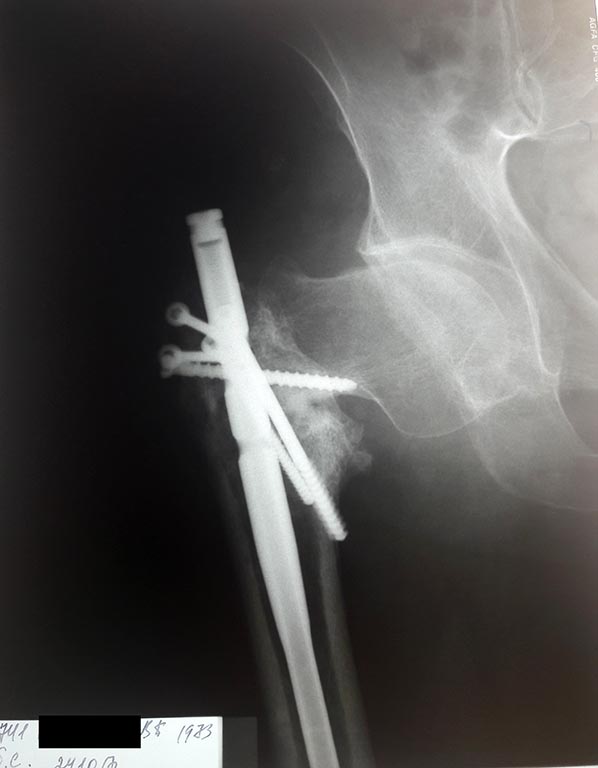

Приобретенная деформация правой бедренной кости в в/3 со смещением

укорочением правого бедра на 5 см. Ложный сустав в/3 правого бедра со

смещением, после остеосинтеза блокируемым штифтом, осложненный миграцией

шурупов.

травма в январе 2016 года, в быту. Лечился по месту жительства скелетным

вытяжением, затем оперирован блокируемым штифтом. На контрольной

рентгенограмме имеется миграция винтов и деформация в/3 правого бедра,

перелом не сросся. Что можно сделать в данной ситуации?